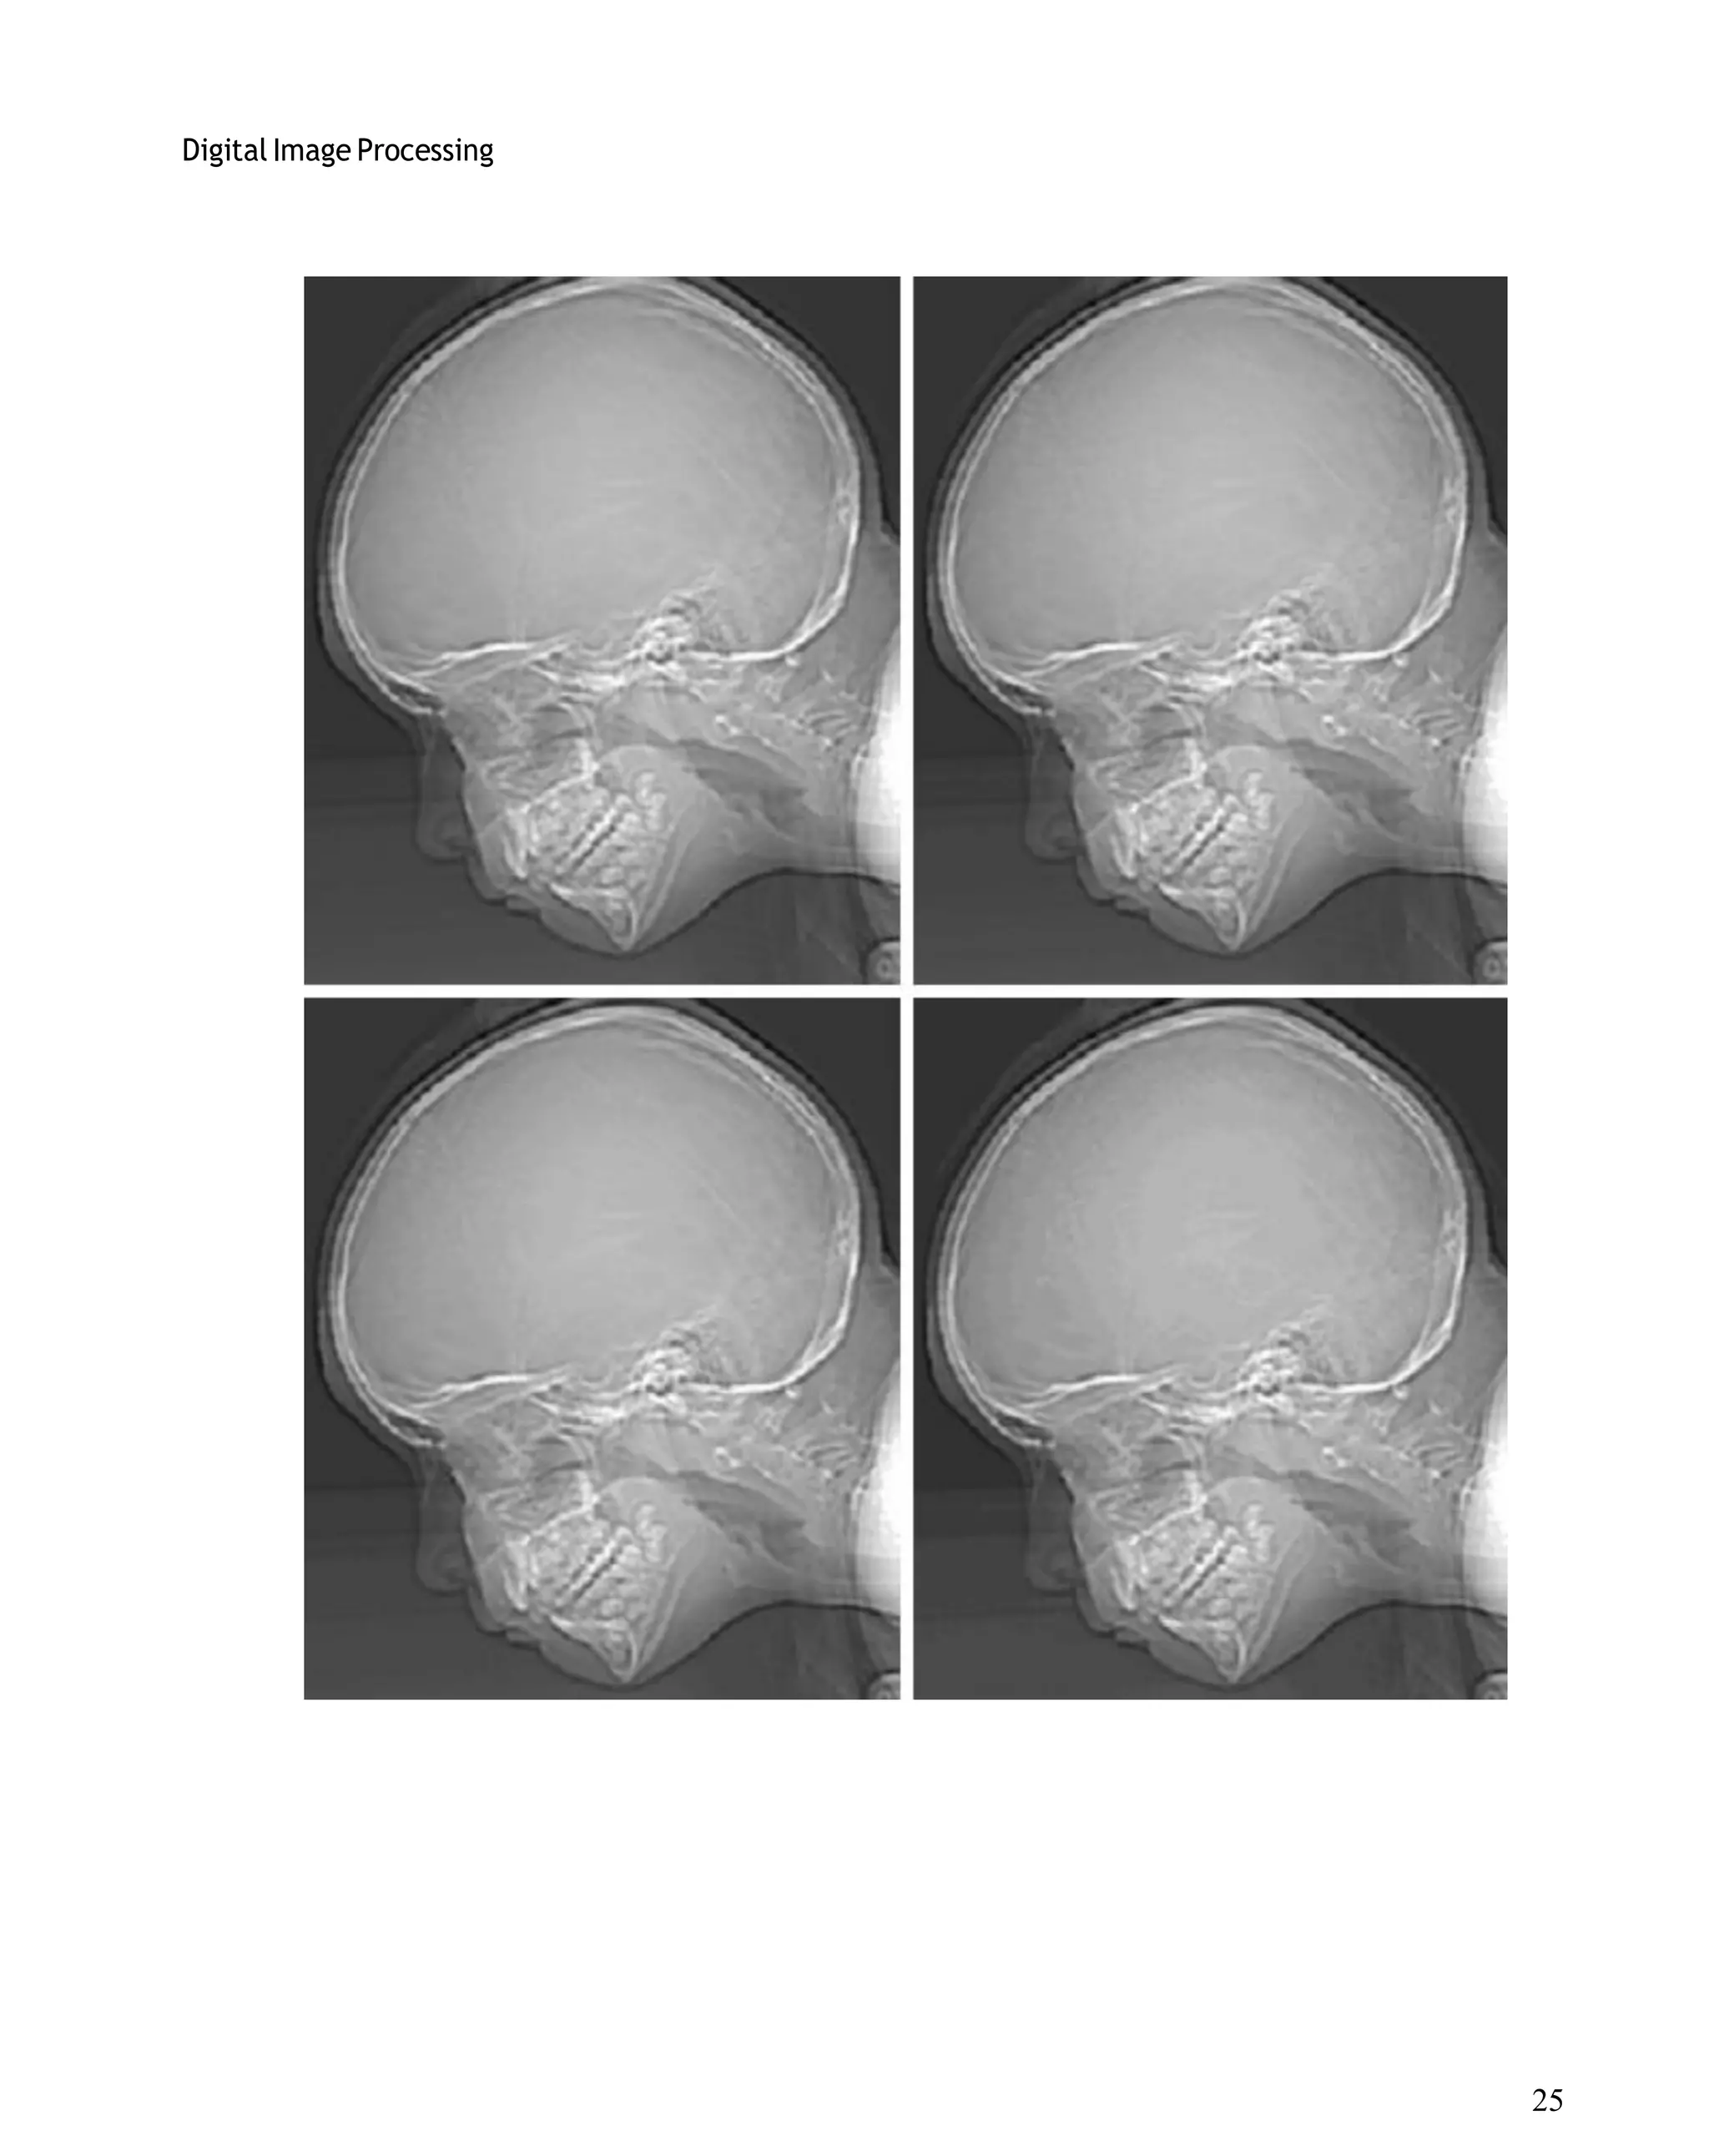

levels from 256 to 2, in integer powers of 2.Figure 7.3(a) is a 452*374 CAT projection image,

displayed with k=8 (256 gray levels). Images such as this are obtained by fixing the X-ray source

in one position, thus producing a 2-D image in any desired direction. Projection images are used

as guides to set up the parameters for a CAT scanner, including tilt, number of slices, and range.

Figures 7.3(b) through (h) were obtained by reducing the number of bits from k=7 to k=1 while

keeping the spatial resolution constant at 452*374 pixels. The 256-, 128-, and 64-level images

are visually identical for all practical purposes. The 32-level image shown in Fig. 7.3 (d),

however, has an almost imperceptible set of very fine ridge like structures in areas of smooth

gray levels (particularly in the skull).This effect, caused by the use of an insufficient number of

gray levels in smooth areas of a digital image, is called false contouring, so called because the

ridges resemble topographic contours in a map. False contouring generally is quite visible in

images displayed using 16 or less uniformly spaced gray levels, as the images in Figs. 7.3(e)

through (h) show.

Fig. 7.3 (a) 452*374, 256-level image (b)–(d) Image displayed in 128, 64, and 32 gray levels,

while keeping the spatial resolution constant (e)–(g) Image displayed in 16, 8, 4, and 2 gray

levels.